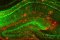

» Сбои в развитии нервной системы у эмбриона связали с деменцией [20/06 20:11]